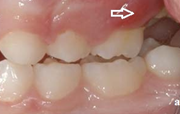

prognaatne hambumus, ülemised eeshambad on ettepoole alumiste suhtes ja eest

progeenne hambumus; alumised eeshambad on ettepoole ülemiste suhtes;